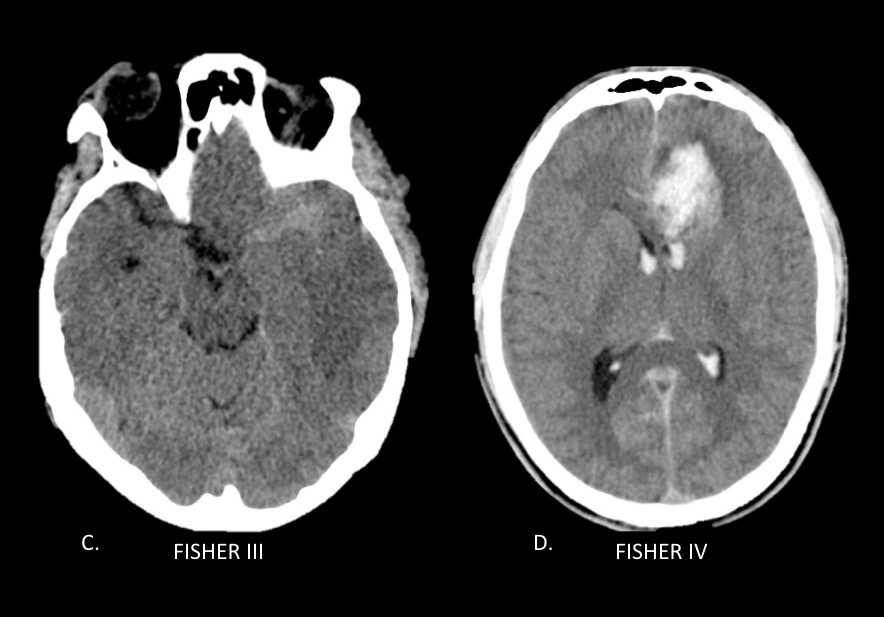

La escala de Fisher es un índice de riesgo de vasoespasmo basado en un patrón de hemorragia definido por tomografía sin contraste (TC) (ver Tabla 5), y la escala de Fisher modificada (también conocida como escala de Classen) es un índice similar de riesgo de isquemia cerebral tardía por vasoespasmo (ver Tabla 6).

| Tabla 5. Escala de Fisher en tomografía para la valoración del riesgo de vasoespasmo en la HSA | |

| Grado | Patrón de HSA en TC de cerebro sin contraste |

| 1 | No HSA o hemorragia intraventricular (HIV) |

| 1 | HSA difusa o capa fina en todas las capas verticales (en cisura interhemisférica, cisterna insular, cisterna ambients) de menos de 1 mm de espesor |

| 2 | Hematoma localizado y / o capas verticales de 1 mm o más de espesor |

| 3 | Hematoma intracerebral o intraventricular con sangre subaracnoidea difusa o sin sangre |

Fig. 1a. Escala de Fisher modificado en TC de cerebro sin contraste, cortes axiales. A. Fisher I y B. Fisher II.

Fig. 1b. Escala de Fisher modificado en TC de cerebro sin contraste, cortes axiales. C. Fisher III y D. Fisher IV.